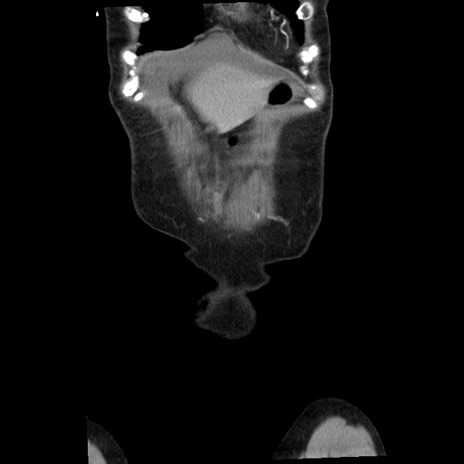

横断像

【症例】80歳代女性

【主訴】腹痛

【現病歴】8時間前から腹痛あり来院。

【既往歴】糖尿病、脂質異常症、子宮体癌にて子宮全摘術

【身体所見】意識清明・会話良好だが腹痛で苦悶様、全腹部にわたって反跳痛と圧痛あり

【データ】WBC 13600、CRP 0.14、LDH 224、CK 90